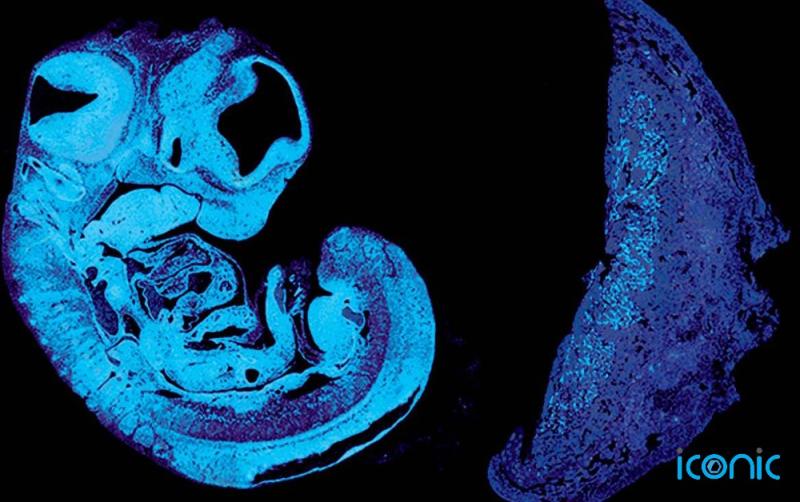

In a study of genetically-engineered embryonic mice, published today in Developmental Cell, the scientists found that the foetus produces the signal, known as IGF2, to encourage the growth of blood vessels in the placenta, and that this involves a “tug of war” between genes inherited from the mother and father.

The response of blood vessels in the placenta to IGF2 in mice is mediated by the protein IGF2R. Genes that produce IGF2 and IGF2R are “imprinted”, with molecular switches that identify their parental origin, and these can switch them on or off.